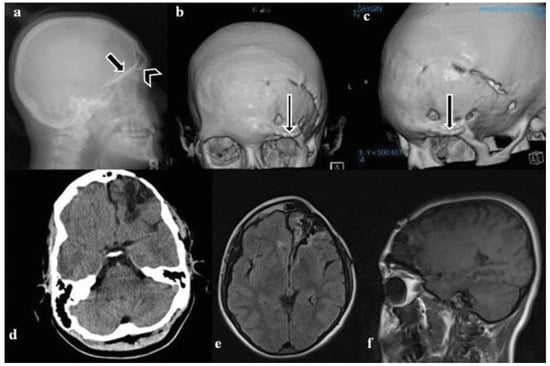

:Case Report